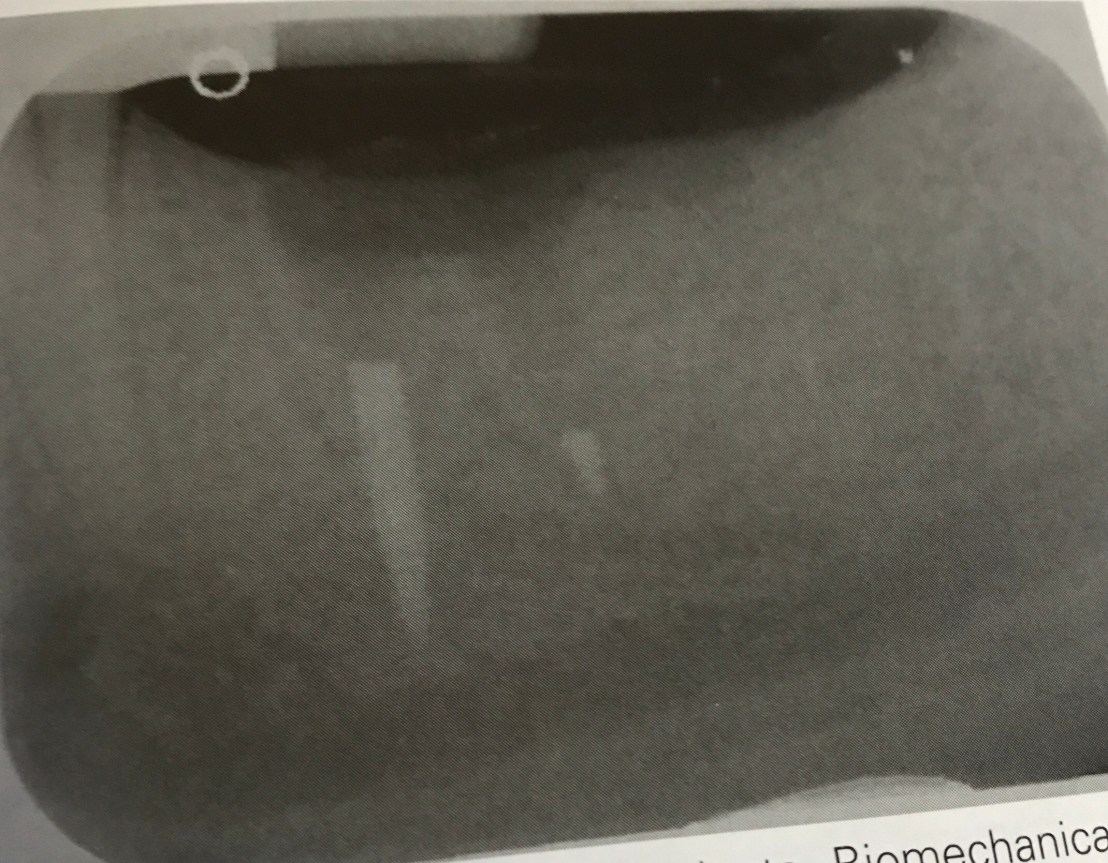

รูปนี้อธิบายในบริเวณ anterior mandible ซึ่งเป็นตำแหน่ง ideal ต่อการฝังมาก เพราะมักมีคุณภาพและปริมาณ cortical bone ที่ดี แต่จากทิศทางการ resorp การวางตำแหน่งก็อดจะไปทางชนด้าน ligual cortical plate ไม่ได้

เพราะ pattern การ resorp ที่มาจาก buccal จึงเกิด angulation ที่ต้องระวัง